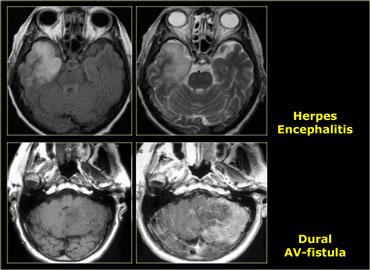

Các Tổn Thương Giả U

Nhiều tổn thương không phải u có thể bắt chước hình ảnh u não.

Áp xe có thể bắt chước hình ảnh di căn.

Bệnh xơ cứng rải rác có thể biểu hiện dưới dạng tổn thương giống khối có ngấm thuốc, còn được gọi là xơ cứng rải rác dạng u (tumefactive multiple sclerosis).

Tại vùng cạnh hố yên, cần luôn xem xét khả năng có phình động mạch.

Các bệnh lý nhiễm trùng và tổn thương mạch máu cũng có thể bắt chước hình ảnh u hệ thần kinh trung ương.